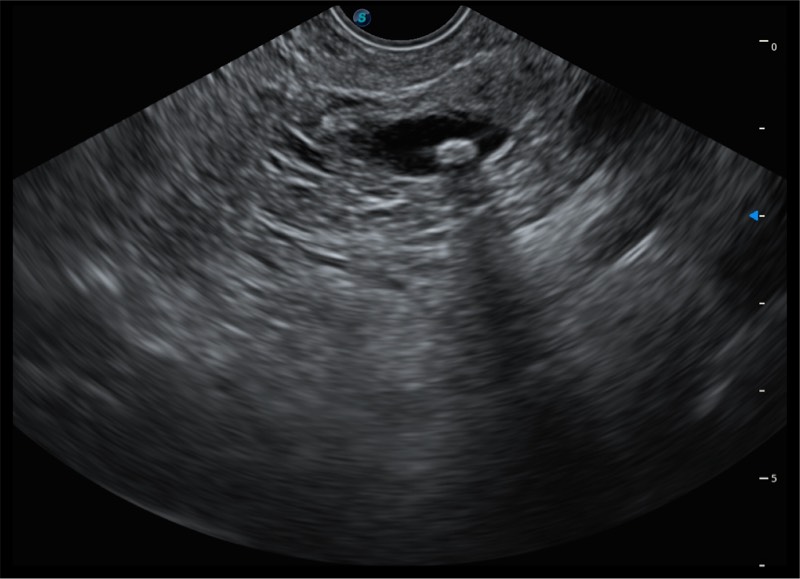

基于二十年的超声技术积累,milan米兰提供了最新一代的独立超声主机,在提供高质量图像的同时满足多学科使用。具备常见多普勒技术并提供弹性成像、声学造影等高端影像技术。新一代传感器具有更强的抗干扰能力并减少图像伪影。

4-12MHZ宽频输出